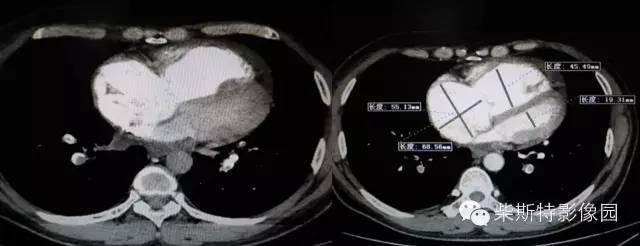

第二大名捕:肺动脉CTA

红色箭头所指处即栓塞导致的充盈缺损,从横断位、冠状位、矢状位三个层面观察,造影剂为高密度白色,而栓子的存在导致造影剂无法充填,从而表现为黑色的低密度影。俗话说的好:长江后浪推前浪!肺动脉CTA的本领已经基本超越其“大哥”肺动脉造影!还可以估测房室大小!